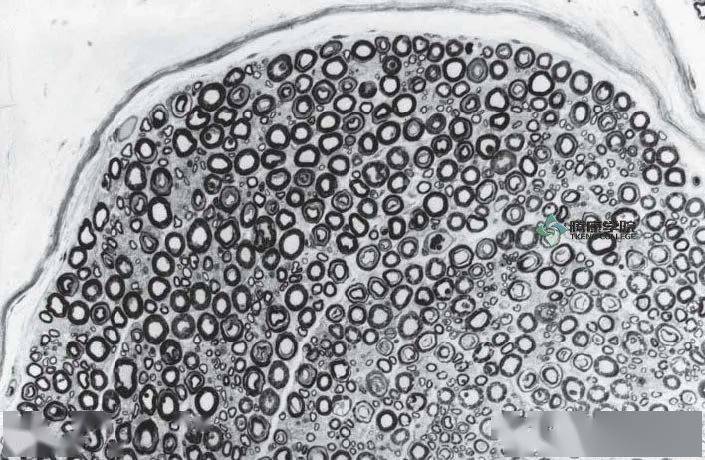

有髓神经纤维 神经外膜 神经内膜 神经束膜 神经横断面

图23 有髓神经纤维束横切面光镜图 (1轴突 2髓鞘 3施万细胞核 4神经束